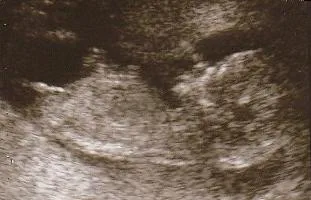

Das Foto des hier gezeigten Kindes in ALSO Er wurde zwischen Woche 11 und 13 der Schwangerschaft genommen. Die Knolle scheint in einem zu sein Position Horizontal, parallel zur Säule, die angeben, dass sie ein Mädchen ist, aber der Form Aus dem Staatsstreich ähnelt es den Genitalien eines Mannes. Es ist schwer zu sagen, was Sex ist, oder?

Das Kind, das drinnen ist LINKS Die Einheit des Genital -Tubulus hier befindet sich in einer 30 -köpfigen Superieur -Ecke. Die Wahrscheinlichkeit von C'est sieht ebenfalls wie ein Penis und ein Hodensackbeutel aus. Das Kind, das drinnen ist ALSO Er hat eine Genitalrolle, die horizontaler als sein Körper ist, parallel zur Wirbelsäule, also ist er wahrscheinlich ein Mädchen.

Der Unterschied bei diesen beiden Kindern ist ziemlich akzentuiert, wird jedoch nicht immer so deutlich beobachtet.